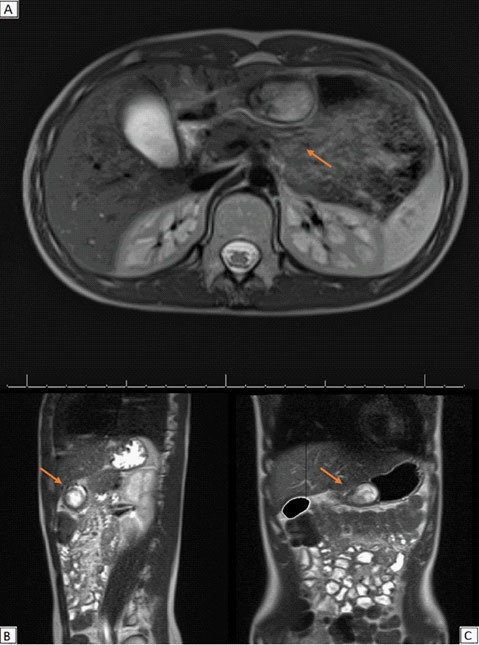

Surgery: Two days after the admission, the patient underwent to surgery. Laparoscopy confirmed the origin of the mass from the gastric antrum. As enucleation of the tumour was not feasible, a laparoscopic pylorus sparing antrectomy with a gastro-pyloric anastomosis was performed (Figure 5).

Figure 5:Shots from laparoscopic surgery – (A): Presence of a gastric mass located at the anterior wall of the gastric antrum was confirmed; (B): After opening the stomach wall, the mucosal-covered mass was shown; (C): Outcomes of gastro-pyloric anastomosis after antrectomy; (D): Removal of the mass using an endobag.